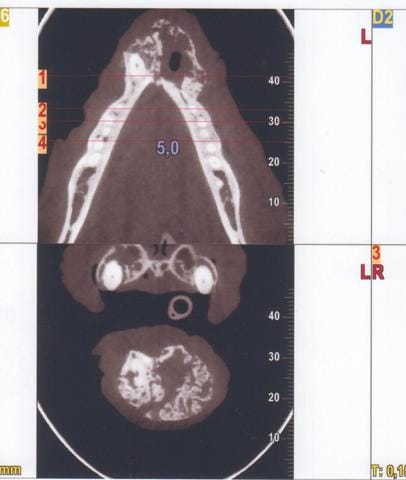

Cône Beam New Tom 5G

Technique : Examen des mâchoires en section axiale ; images natives de 0,1mm ; reconstruction MPR et 3D 0,1mm temps d’exposition total : 7.3s ; mAs : 23.08 ; kV 110kV ; CDTi/V (dose délivrée / surface exposée) : 3.27 mGy

Description

Mise en évidence d’une masse homogène se développant dans la base du menton avec néoformation osseuse de type proliférative.

Centre de la lésion au niveau de l’alvéole de la canine gauche absente et extension hauteur de PM3 pour la mandibule gauche et Pm2 pour la mandibule droite.

Limite carcinologique appréciée (5mm) en mésial des carnassières.